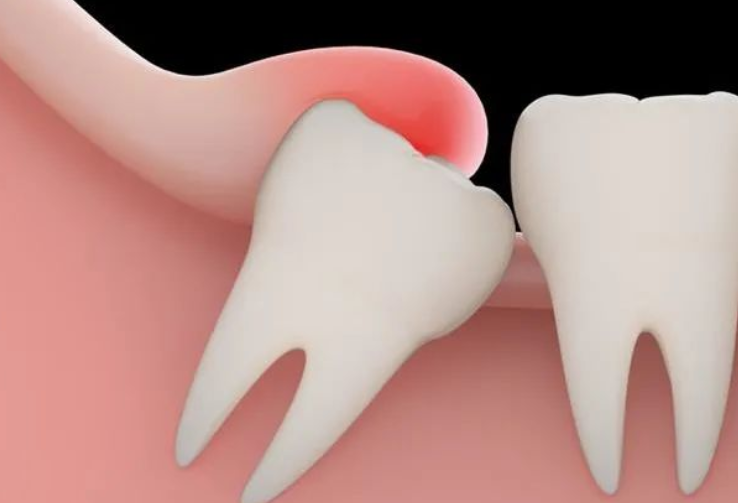

1、拔阻生智齒:拔智齒是這家醫(yī)院很不錯的項目之一,醫(yī)生在做阻生和埋伏智齒拔除的時候,手法都比較細膩,形成的創(chuàng)口比較小,術后恢復的會比較快。

我的口腔當中左側下面的智齒經常會導致我牙齦疼痛,后來我才知道,這是因為這個牙齒有埋伏現(xiàn)象,為了能夠使這顆牙齒帶來的疼痛快點得到消除,我在南方醫(yī)科大學珠江醫(yī)院的牙科做了拔智齒的手術。

拔智齒過程中

在拔智齒的時候,醫(yī)生給我使用了麻藥,所以拔智齒的時候雖然有點疼痛感,但并不是特別的嚴重。工作手術手法比較輕柔,做完之后創(chuàng)口恢復的也挺快的,不到兩周的時候就已經看上去恢復如初了,不過醫(yī)生告訴我還需要做好護理,要在一個月之后才能夠真的恢復好。

拔智齒之后

現(xiàn)在我拔完智齒已經兩個多月了,果然沒有了這顆智齒之后,我的牙齒再也沒有出現(xiàn)發(fā)炎疼痛的癥狀,而且口腔的整體健康度都比較好。